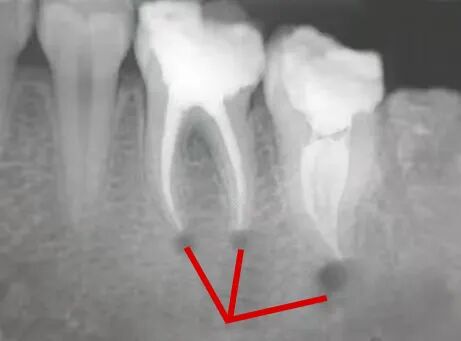

🔎根尖炎症

X光拍片为什么要等看牙为什么要拍片?非专业人士如何看懂自己的牙片!_https://www.jmylbn.com_新闻资讯_第16张

△根尖那里有黑色的阴影,说明牙根尖有炎症病变,这种多为根尖炎。